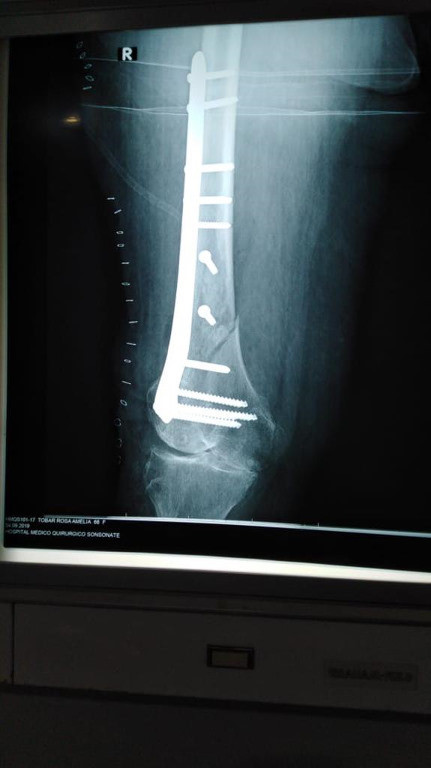

Imágenes de ortopedia y traumatología

Envíado por Dr. José Israel Flores Hernández